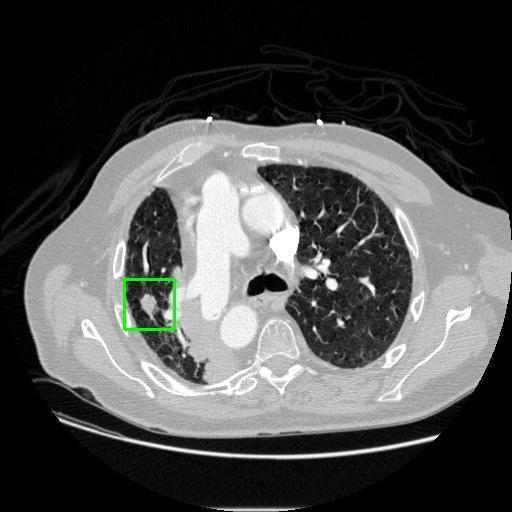

We developed an AI-based system using deep learning models for analyzing lung CT scans to detect and classify pulmonary nodules. We chose the YOLOv11 architecture for its enhanced object detection capability and adapted it specifically for medical imaging, incorporating pixel-level precision and severity classification.

Classification into three severity levels with colored bounding boxes.

Designed a severity classification system that categorizes nodules into null, moderate, and severe using colored bounding boxes, assisting in rapid clinical decision-making.